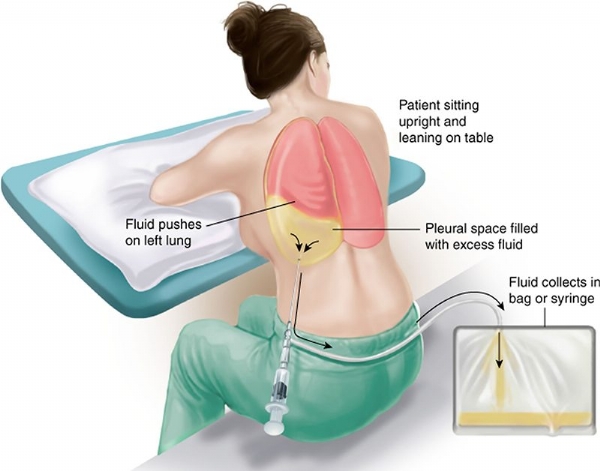

- Tràn dịch màng phổi không rõ nguyên nhân.